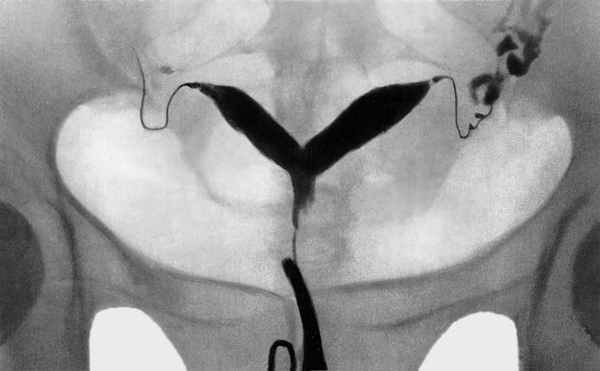

- Проведение гистеросальпинграфии. Представленная методика является наиболее точной и достоверной из всех существующих. В процессе исследования в полость матки женщины с помощью специального катетера вводится особое контрастное вещество, после этого — делается снимок, на котором отчетливо будет видна пара ответвлений с характерным утолщением между ними.

Метросальпингографические данные при двурогой матке

Наиболее характерным признаком седловидной матки при гистеросальпингографии является выявление на рентгенограммах в дне матки небольшого углубления в виде седла [6].

На гистерограммах при такой патологии определяются два устья маточных труб, а дно как бы выступает в полость матки в виде гребня [4].

Однако, несмотря на высокую информативность этих методов, каждый из них не лишен определенных недостатков. К недостаткам гистероскопии следует отнести инвазивность метода гистеросальпингографии - невозможность исключить нежелательное влияние на организм ионизирующего облучения и магнитно-резонансной томографии - большую стоимость исследования.